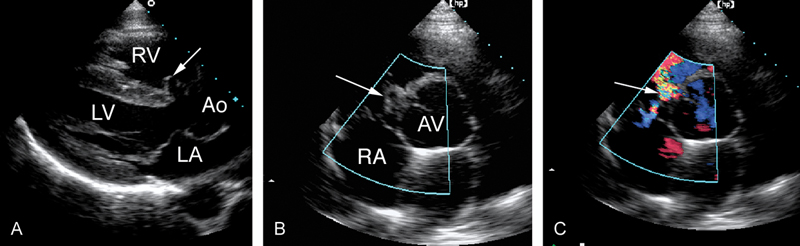

فحوصات تشخيصية لبعض امراض القلب والشرايين التاجية